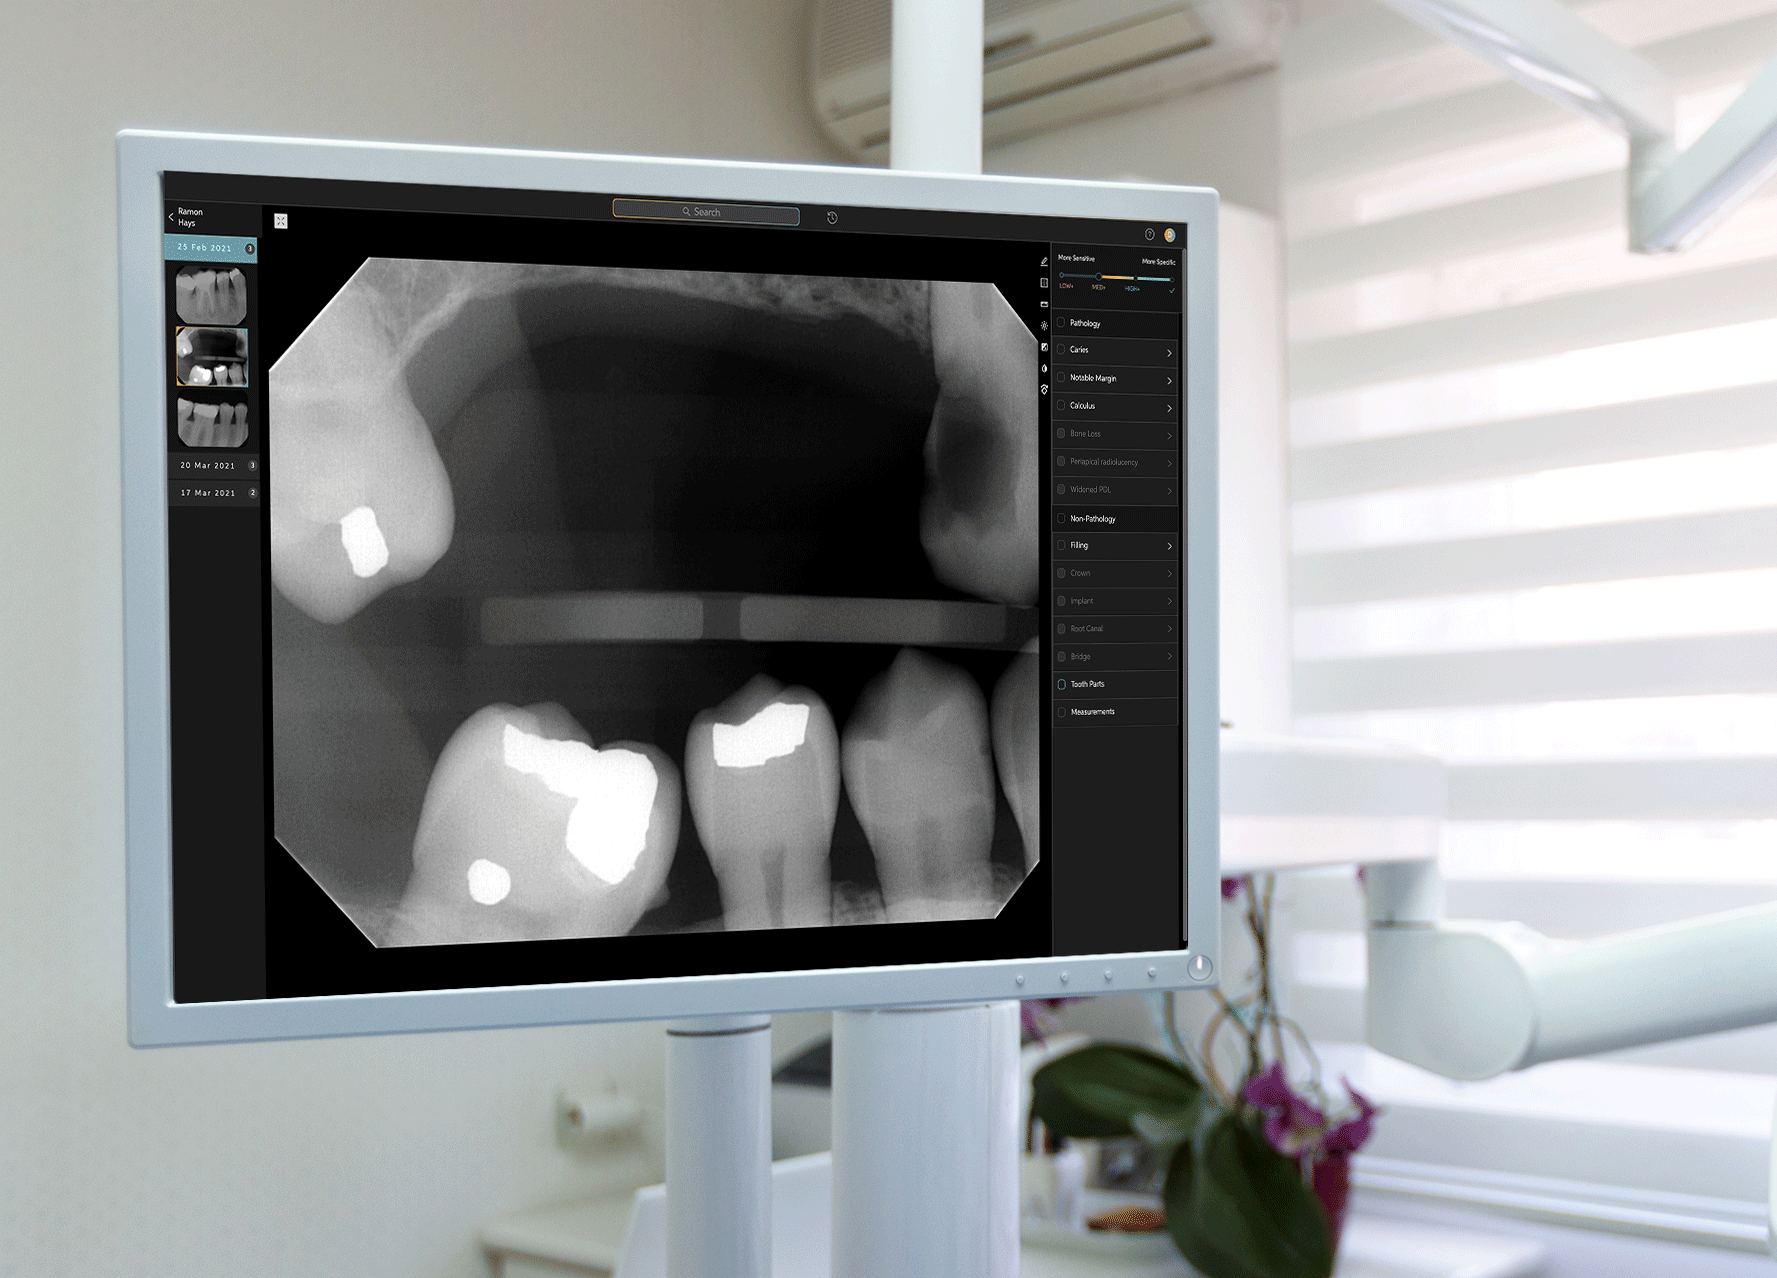

Earlier this week, West Hollywood-based startup Pearl announced that its Second Opinion product had become the first AI-enabled device cleared by the Food and Drug Administration to read dental x-rays. Using the power of artificial intelligence, Second Opinion is meant to help dentists find maladies they’d otherwise miss through the eye test.

Getting FDA clearance is not easy, especially because Pearl had to prove its device could detect a variety of dental conditions (most medical devices have to prove only one capability). Pearl’s CEO, Ophir Tanz, said it was a multi-year undertaking that entailed a 4,000-page clinical trial report.